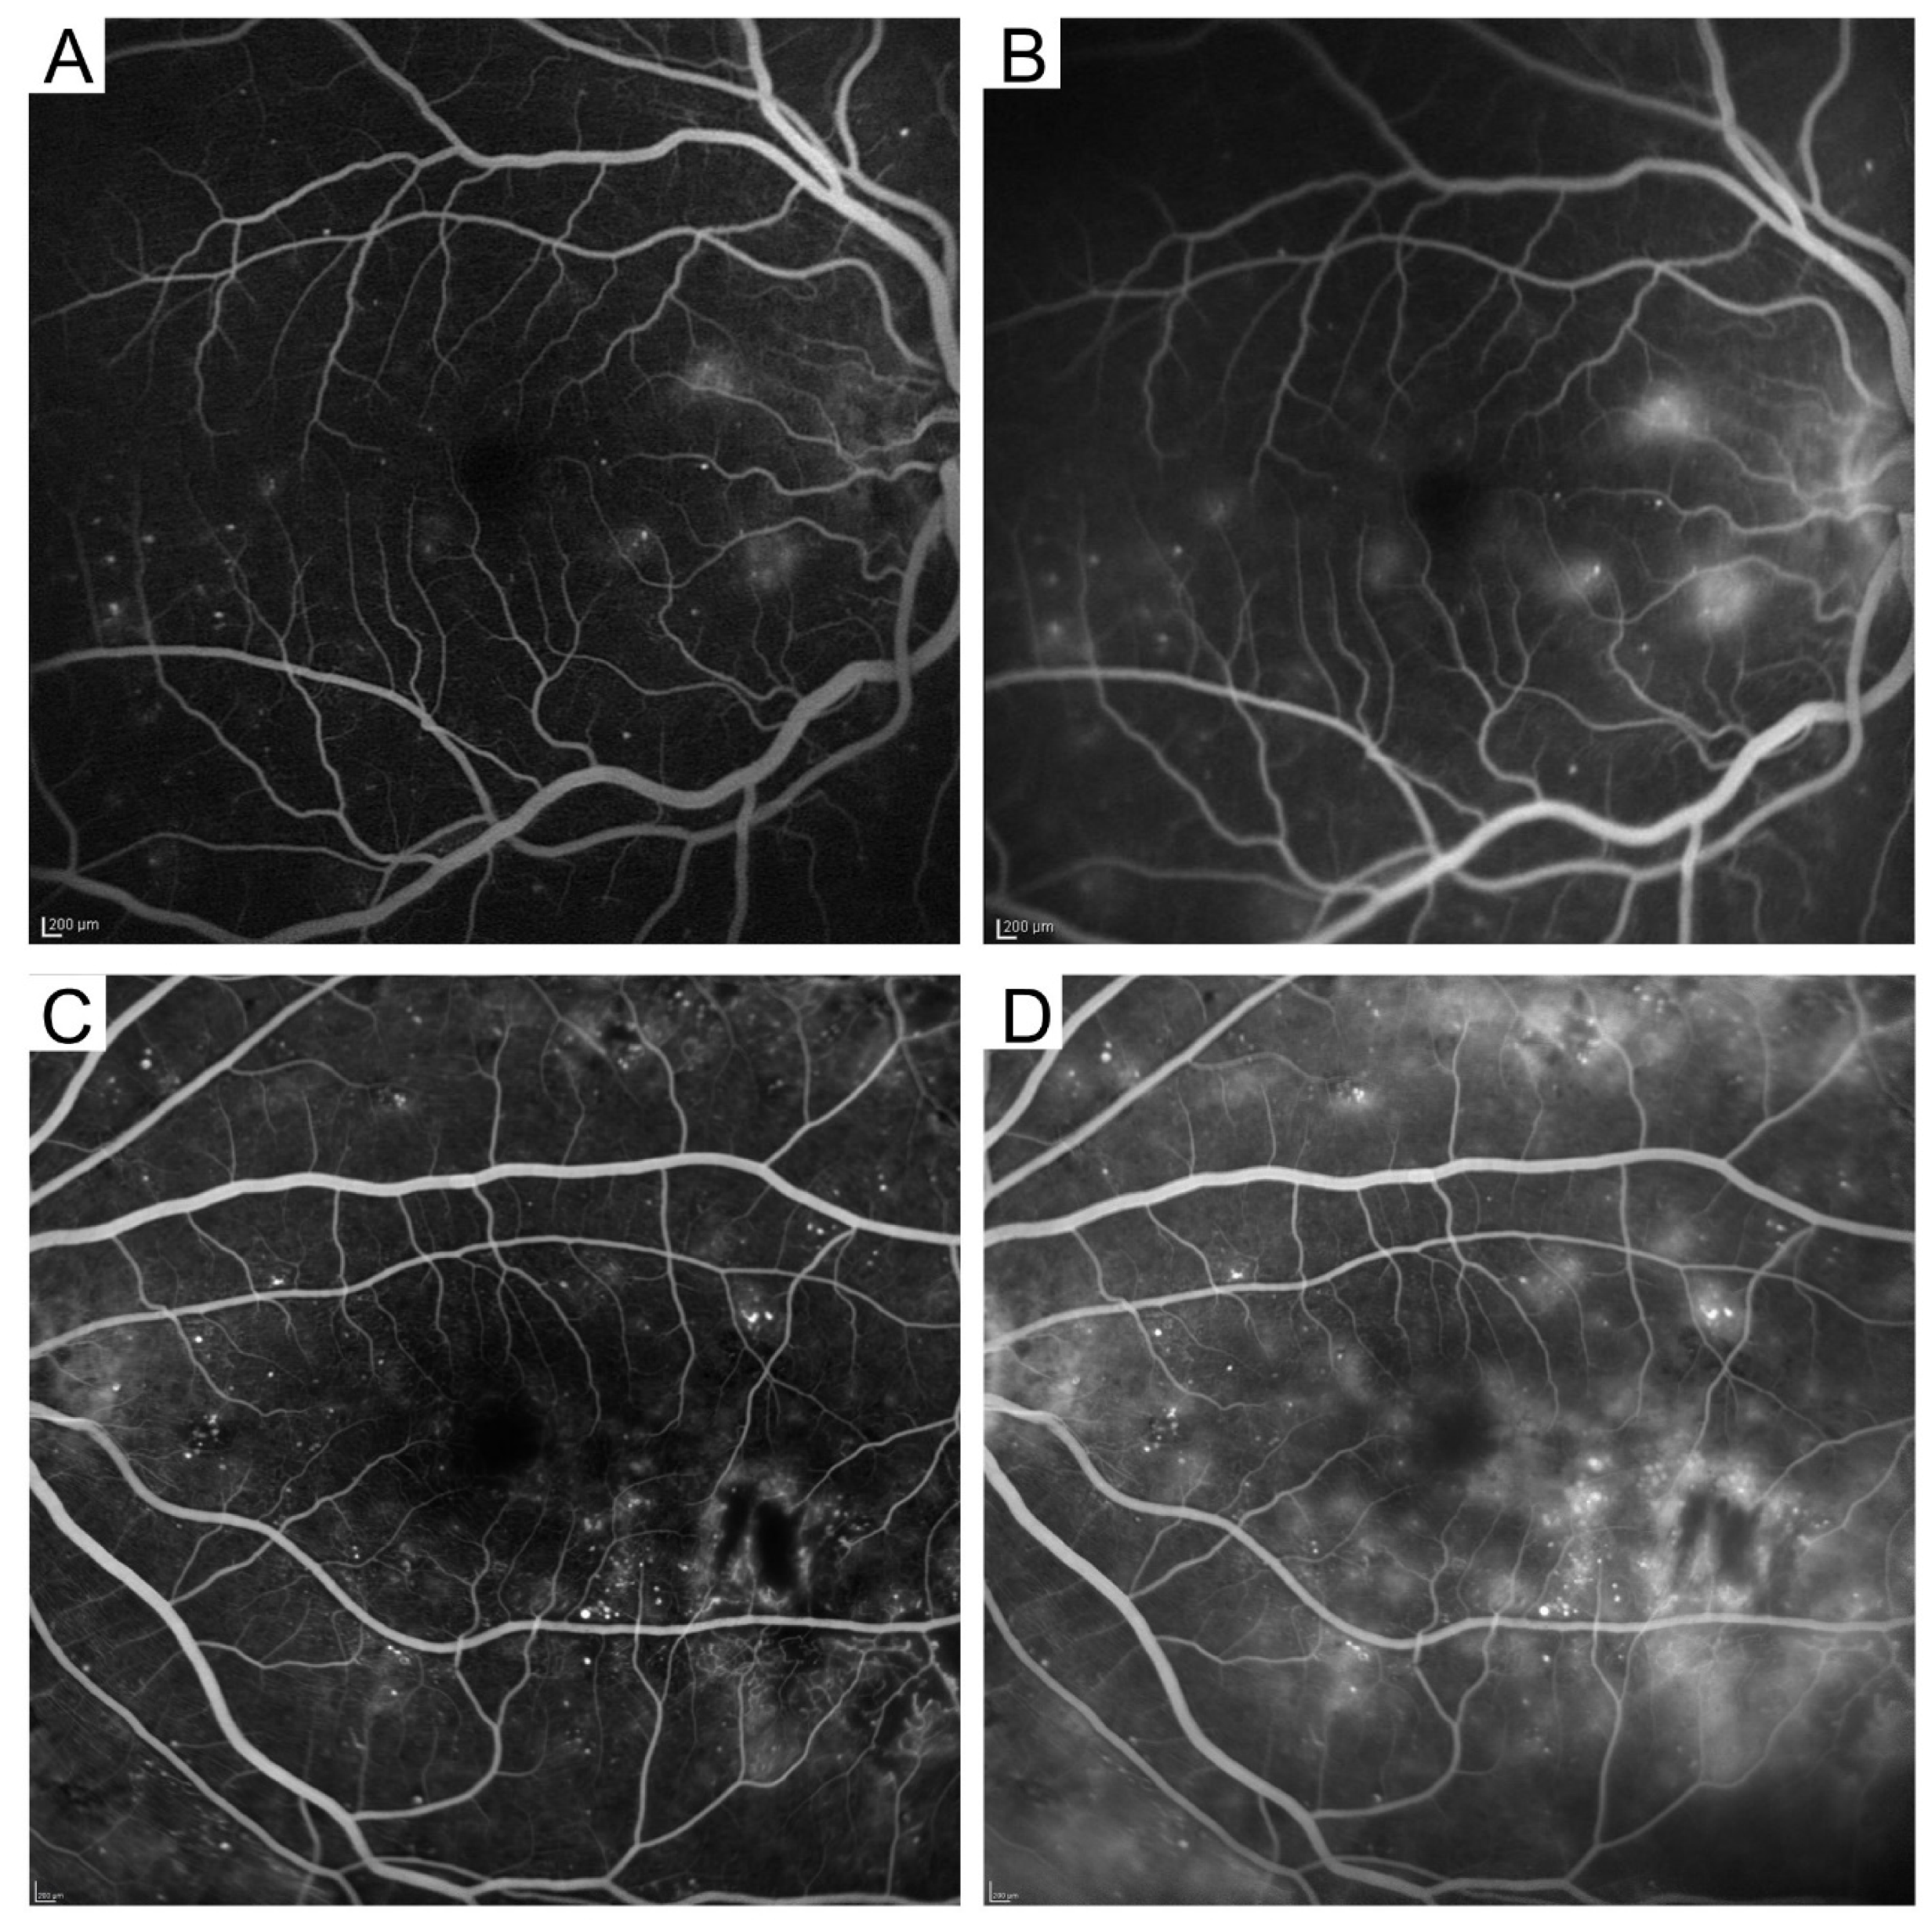

4.1. Fluorescein Angiography

4.2. Indocyanine Green Angiography